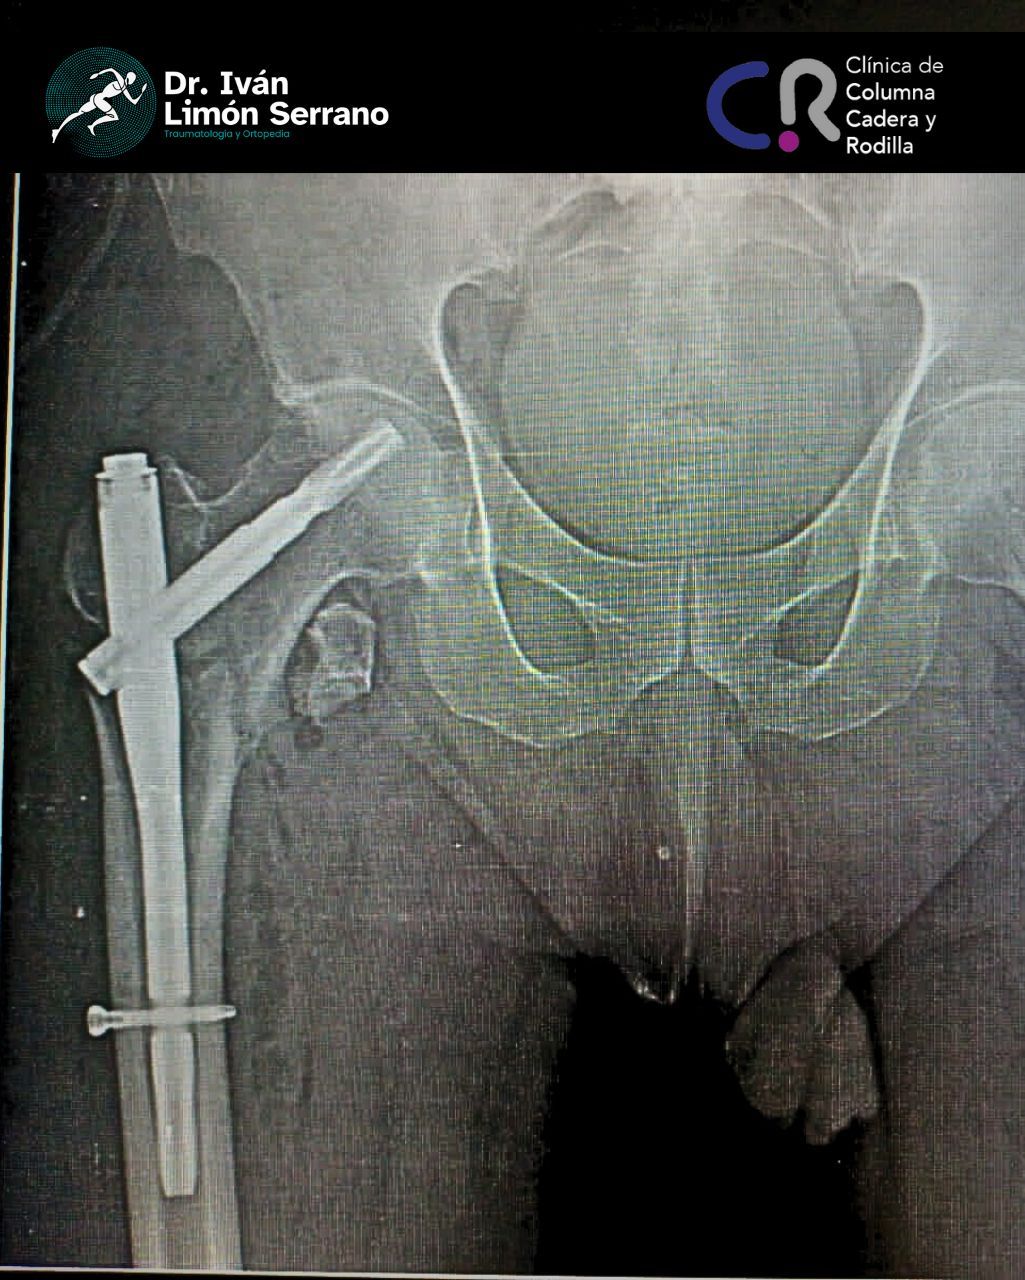

• Prótesis de cadera

• Cirugía cadera

• Artroscopia de cadera